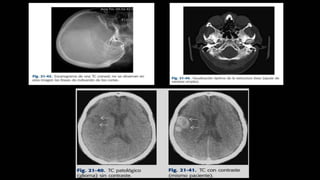

El documento define los conceptos básicos de pixeles, voxels y principios de calidad de imagen en tomografía computarizada. Explica que los pixeles son unidades de información en una imagen y los voxels son unidades de volumen que representan pixeles en secciones de corte. También describe factores como resolución espacial, de contraste y temporal que afectan la calidad de imagen, así como posibles artefactos.